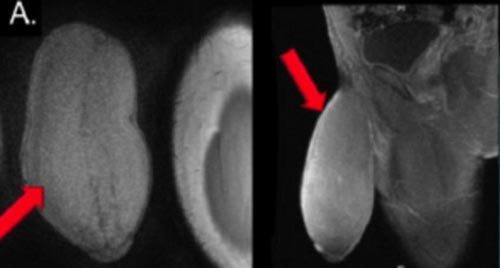

Ảnh chụp X-quang cho thấy dương vật của bệnh nam 17 tuổi phát triển lớn dị thường, gây nhiều bất tiện và khó chịu cho khổ chủ. Ảnh: Journal of Sexual Medicine |

Các bác sĩ phẫu thuật cho chàng trai thực sự bị sốc khi cậu tìm đến chỗ họ than phiền về "súng ống quá khủng". Khi ở trạng thái ỉu xìu, nó có số đo chiều dài gần 17,8cm với chu vi tới 25,4cm, tức là tương đương kích cỡ một quả bưởi. Các chuyên gia phẫu thuật thậm chí mô tả "cậu nhỏ" đặc biệt này có hình dạng của một quả bóng bầu dục.